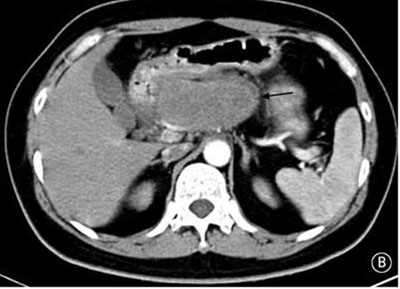

就診時(shí)實(shí)驗(yàn)室檢查結(jié)果顯示嚴(yán)重高血糖(血糖水平為982mg/dL[55mmol/L])。腹部CT檢查顯示胰頭部位出現(xiàn)一個(gè)9cm大小的腫塊(如圖B箭頭所示)??崭寡逡雀哐撬厮綖?30pg/ml(正常值≤80pg/ml)。